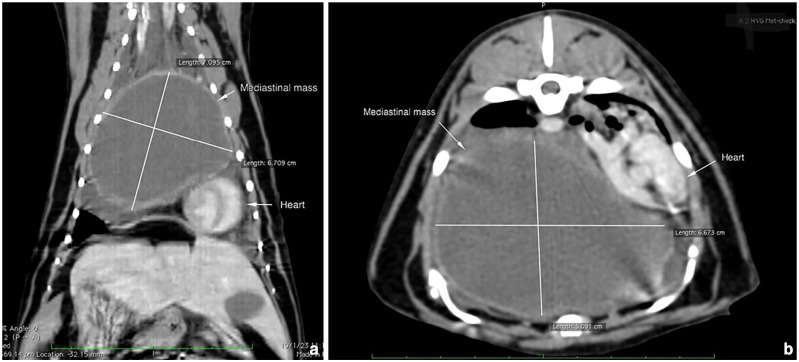

Case summary: A 7-year-old female spayed domestic shorthair cat presented with respiratory distress. Initial diagnostics revealed a large cystic mass in the mediastinum and moderate hyperglobulinaemia. Additional abnormalities were ruled out through thoracic and abdominal CT. The mass was surgically removed, and antibiotic treatment was started based on cytological findings of intralesional bacteria. Histopathology and microbiology confirmed a severe inflammatory reaction pattern compatible with feline eosinophilic sclerosing fibroplasia (FESF) associated with Staphylococcus aureus. After surgery and antibiotic therapy, clinical signs and related abnormalities fully resolved. At the time of writing, 24 months postoperatively, the patient shows no evidence of relapse.

Relevance and novel information: FESF, initially described as an inflammatory condition affecting the gastrointestinal tract, has also been anecdotally reported in other locations, including the retroperitoneum, retropharyngeal region and mediastinum. This report is the second to document a mediastinal presentation without concurrent abdominal involvement, and the first to achieve long-term remission without the use of immunosuppressants. It supports the hypothesis that FESF may represent a characteristic pattern of inflammation secondary to a range of triggers rather than a distinct disease process, indicating that treatment should probably target the specific underlying cause.